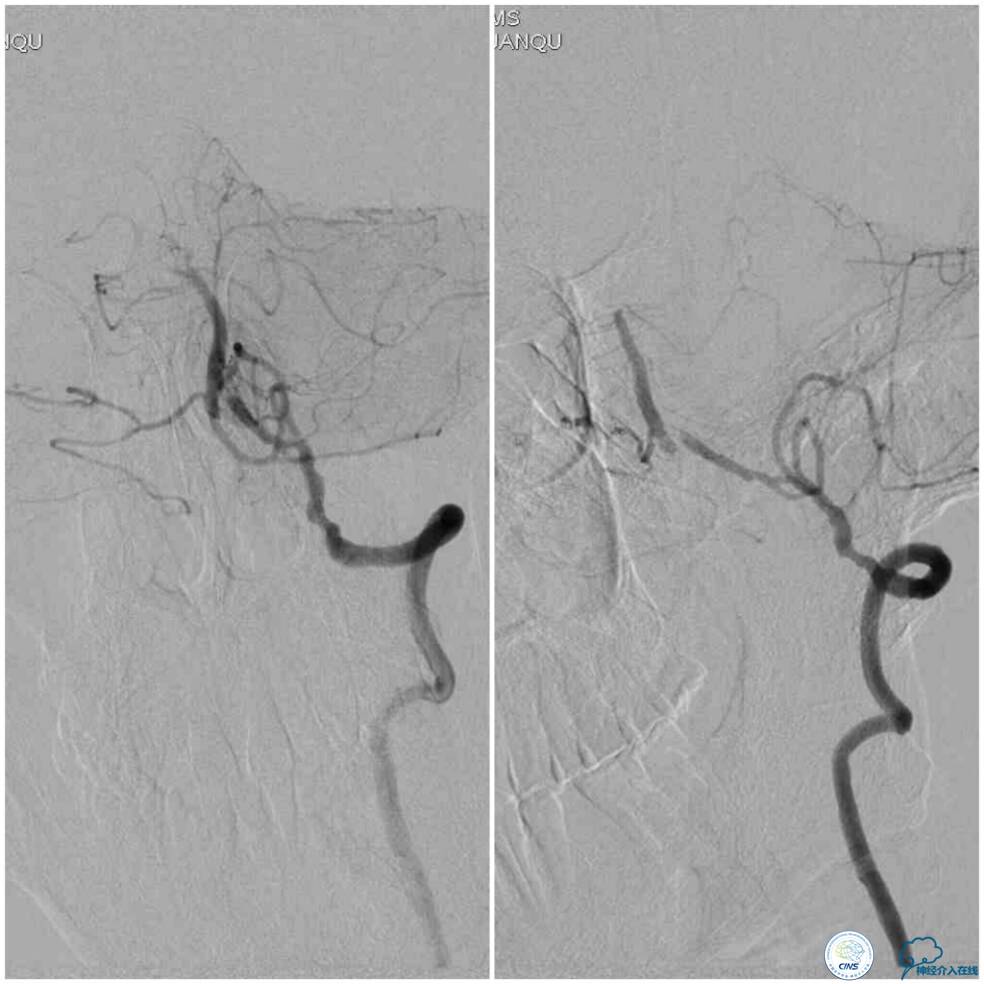

同期行DSA提示右椎动脉V4段发出右PICA后未见顺行显影(图2),左椎动脉V4段-基底动脉汇合处重度狭窄(图3),前循环向后循环的未见明显代偿(图4)。

血栓弹力图检查:AA抑制率98.2%、ADP抑制率47.7%。颅内CTA及后循环CT灌注检查提示:右椎动脉V4段未见显影,左椎动脉与基底动脉汇合处重度狭窄,右椎动脉V4段在汇合点以下有显影(图5);双侧小脑半球低灌注,右侧为著(图6)。